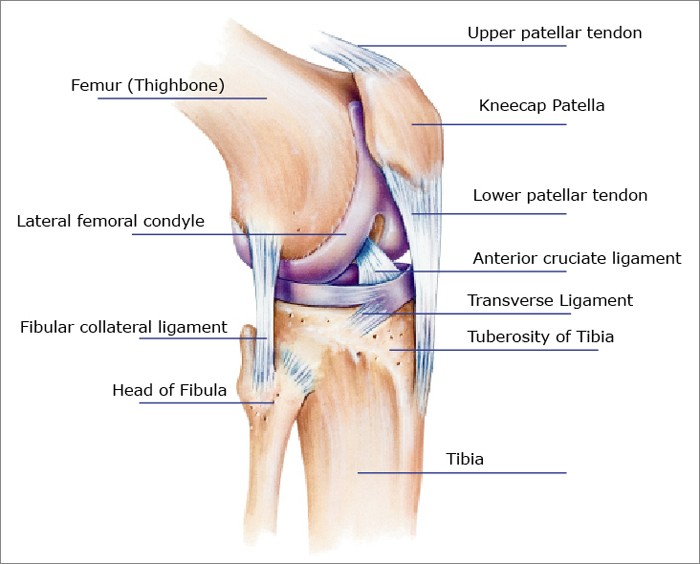

Анатомические изображения менисков и коленного сустава

Раздел: Иллюстрированные советы